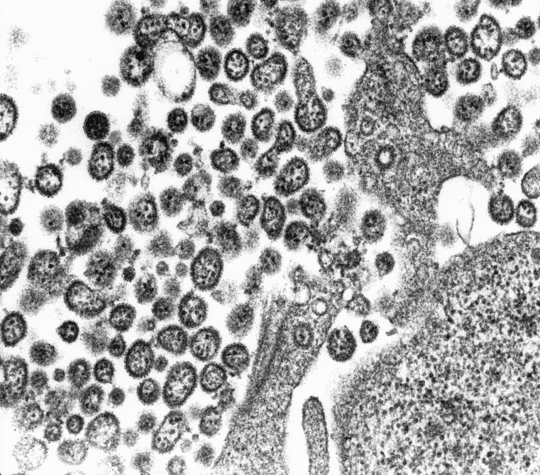

Lassaviren: Arenaviren der höchsten biologischen Sicherheitsstufe 4